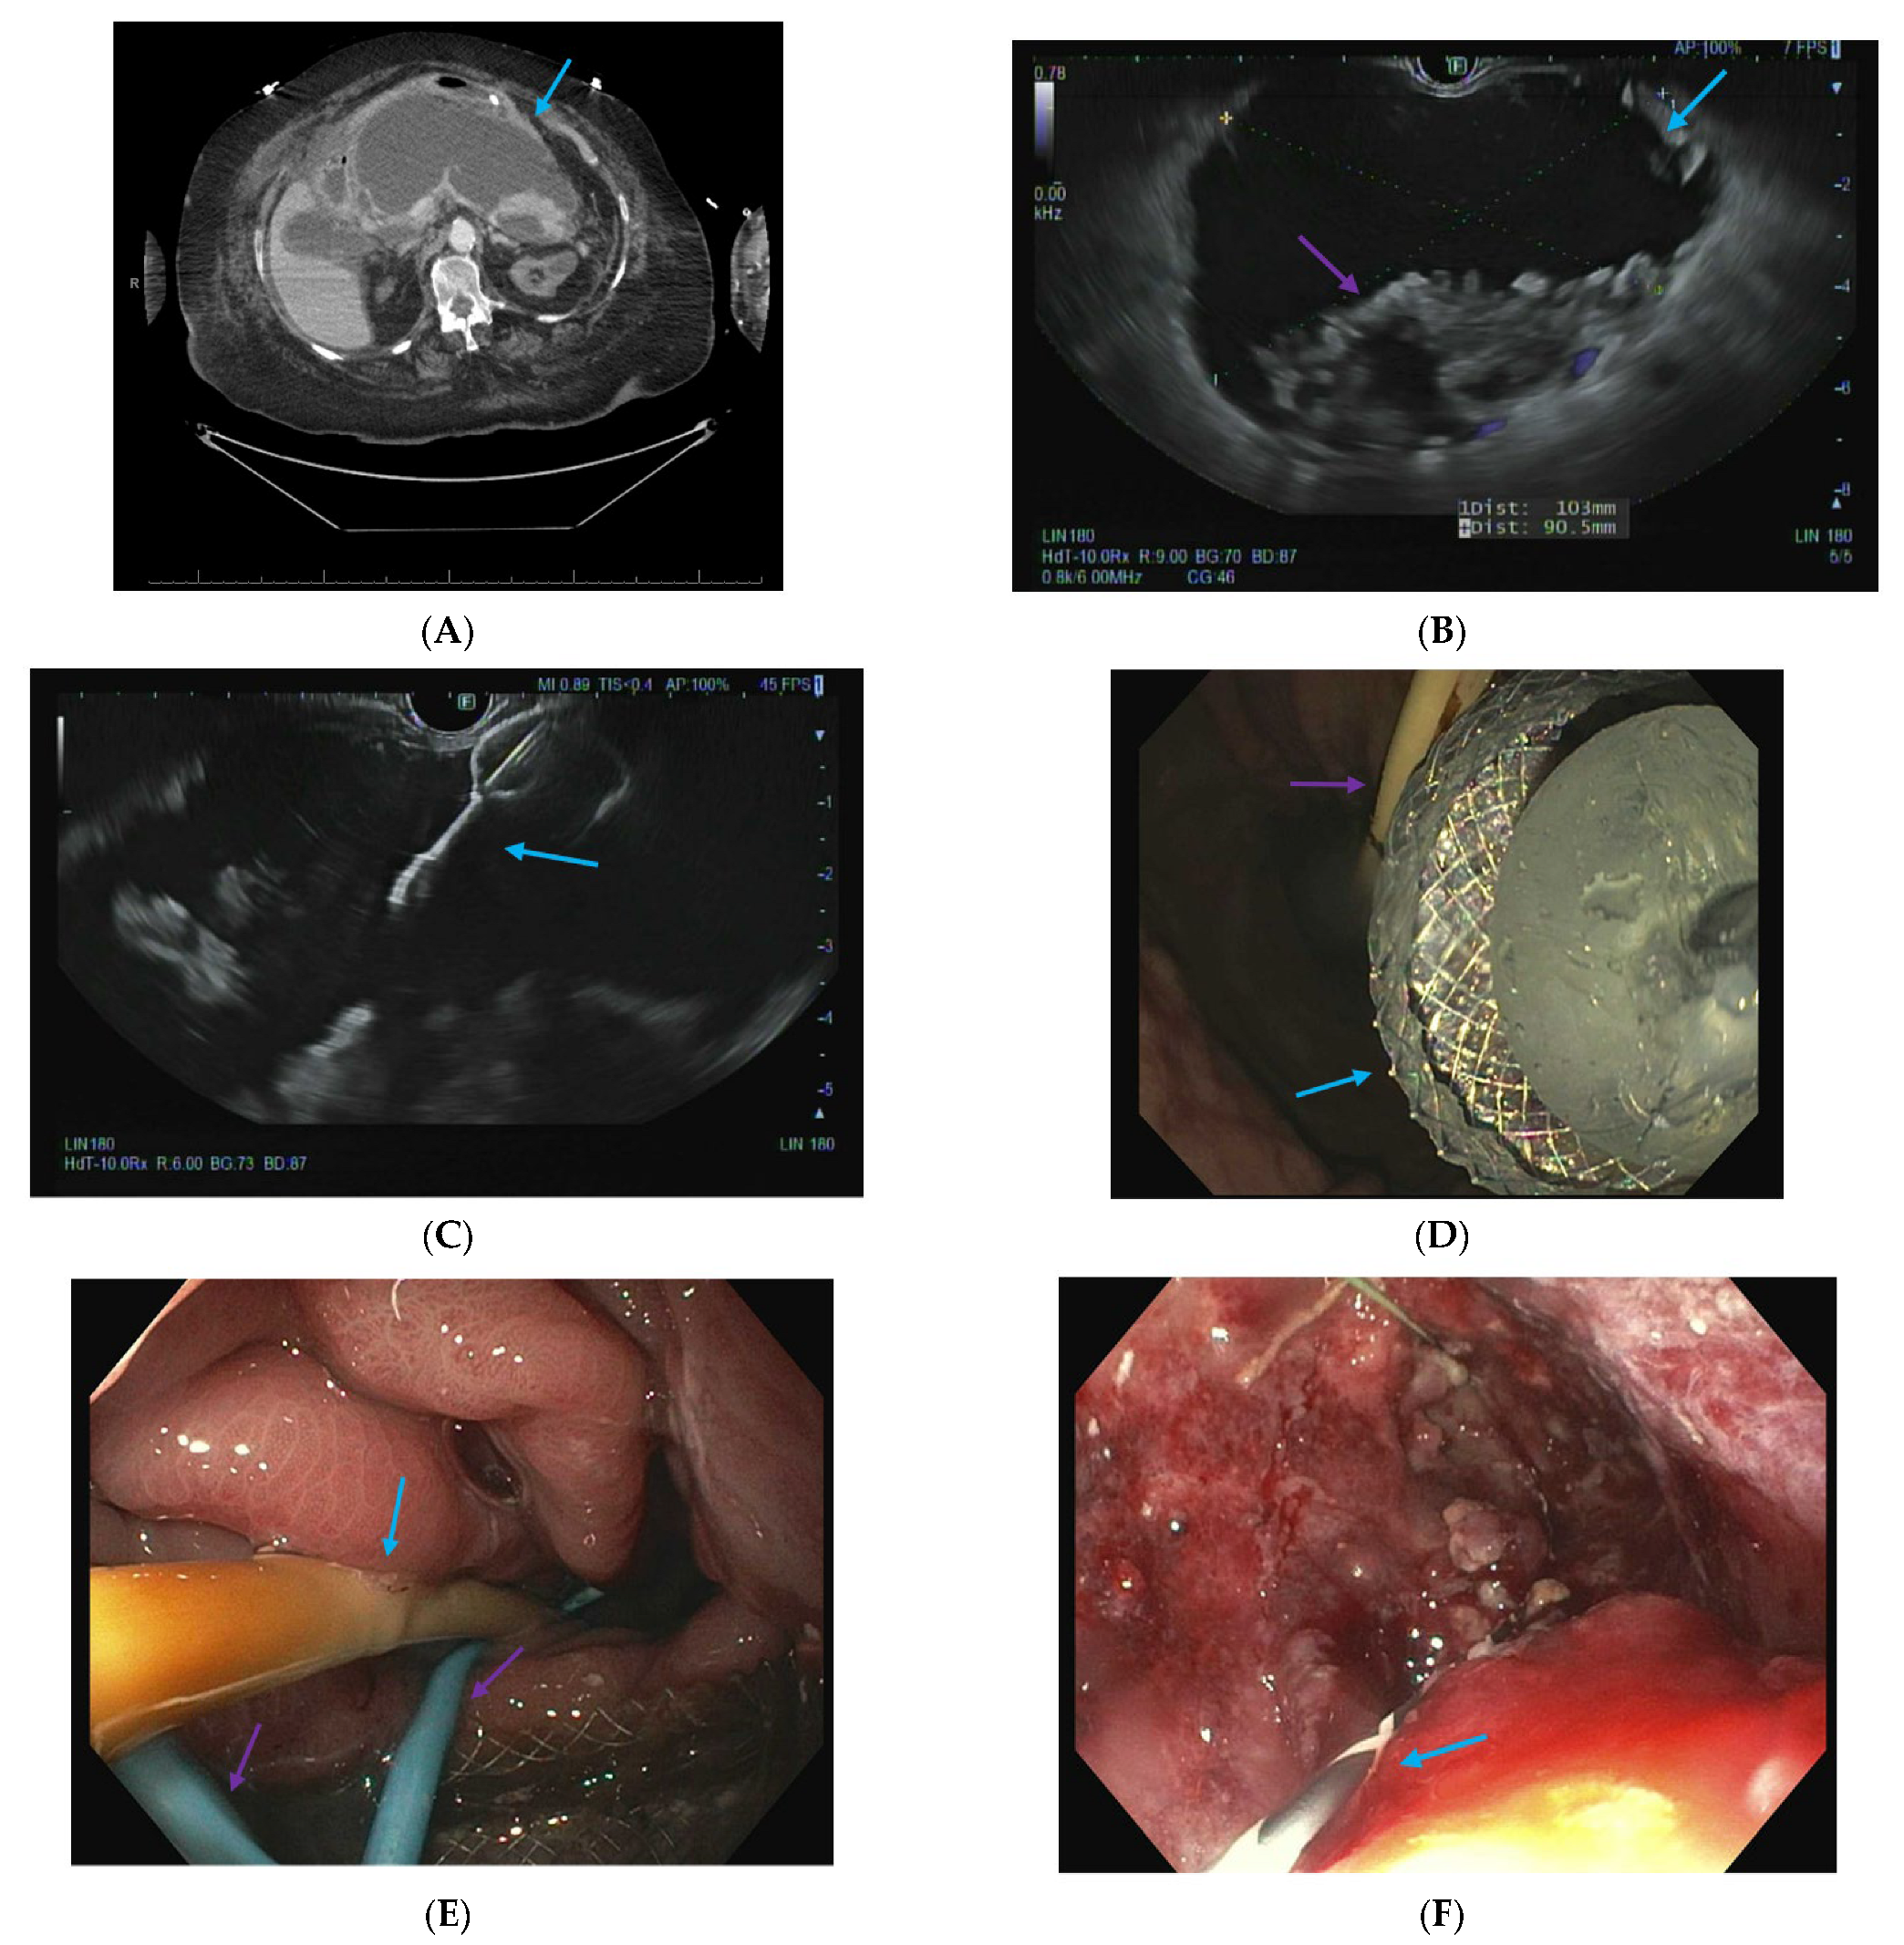

2.4. Endoscopic Ultrasound-Guided Techniques for Walled-Off Pancreatic Necrosis (WON)

2.5. Direct Endoscopic Necrosectomy

2.6. Dual Modality Drainage

2.7. Interventional Radiology-Guided Embolization of Pseudoaneurysms